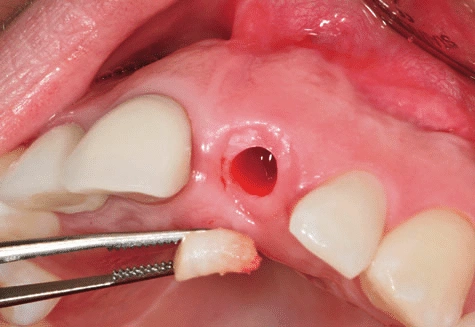

ایمپلنت دندان نیش موفقیتهای زیادی به همراه خواهد داشت و در اغلب مواقع عوارضی به دنبال ندارد اما مانند هر روش جراحی دیگری کاملا بدون عوارض نخواهد بود. مواردی همچون التهاب موقت لثه، درد پس از جراحی، خونریزی مختصر یا در موارد نادر، عفونت ناحیه جراحی ازجمله عوارض ایمپلنت دندان نیش هستند.

از آنجایی که دندان نیش نقش مهمی در ساختار فک و زیبایی دارد، اگر ایمپلنت این ناحیه به درستی صورت نگیرد، میتواند به اعصاب یا ریشه دندانهای مجاور فشار وارد کند. در فک بالا ریشه دندان نیش در نزدیکی سینوس قرار دارد. این امر سبب میشود ایمپلنت دندان نیش بالا نیز همانند ایمپلنت دندان عقل به تخصص قابل توجهی نیاز داشته باشد. رعایت بهداشت دهان و مراجعه منظم به دندان پزشک، در پیشگیری از این عوارض نقش مهمی خواهد داشت.

همانطور که پیشتر بیان شد، دندان نیش بالا در نزدیکی سینوس قرار دارد. از این رو برای انجام ایمپلنت آن به دقت و تخصص بالایی نیاز است. ریشه دندانهای نیش بالا بلند بوده و در جایگزینی آنها باید به گونهای عمل شود که توازن بین دندانهای جلویی و عقبی حفظ گردد.

در برخی شرایط به دلیل تحلیل فک یا نزدیکی به سینوسهای فکی لازم است پیش از کاشت انواع ایمپلنت همچون ایمپلنت دندان طلا، پیوند استخوان یا لیفت سینوس صورت گیرد. برای حداکثر کردن موفقیت در ایمپلنت دندان نیش بالا میتوان از روشهای دقیق مانند ایمپلنت دیجیتالی دندان برای این ناحیه بهره برد و خطای جراحی را به حداقل رساند.